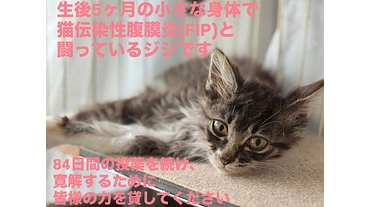

ジジを助けたいです。元野良猫ジジのFIP治療費のお願い。

- 現在

- 460,000円

- 支援者

- 81人

- 残り

- 5日